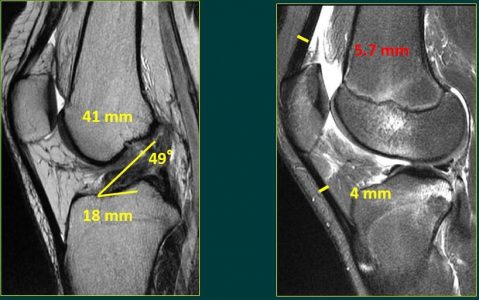

-Εξατομικευμένη τοποθέτηση της περιοχής πρόσφυσης του μοσχεύματος, τόσο στον μηρό όσο και στην κνήμη. Οι περιοχές αυτές πρόσφυσης παρουσιάζουν ιδιαιτερότητες σε κάθε ασθενή. Οι κλασικές μέθοδοι αναπαράγουν με οδηγούς τις περιοχές αυτές με παρόμοιο τρόπο σε όλους τους ασθενείς . Η εξατομικευμένη τεχνική προσδίδει την ιδανική ανατομική αποκατάσταση του συνδέσμου και πιθανότατα και καλύτερη συμπεριφορά του μοσχεύματος (Εικόνα 2).